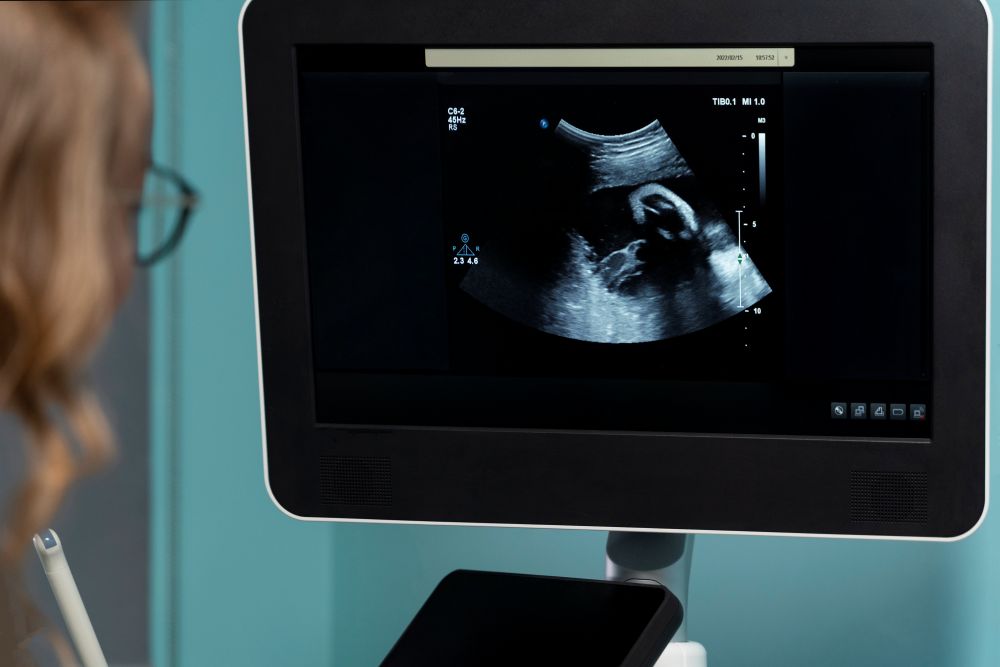

Bei der pränatalen Diagnostik kommt es besonders auf Erfahrung und Fachwissen an. In spezialisierten Praxen liegt der Fokus ausschließlich auf der Untersuchung und Begleitung von Schwangeren. Moderne Ultraschallgeräte ermöglichen hochauflösende 3D- und 4D-Darstellungen, mit denen kleinste Auffälligkeiten früh erkannt werden können. Das sorgt nicht nur für präzise Diagnosen, sondern gibt Eltern auch ein beruhigendes Gefühl. Eine Praxis wie die Ultraschallpraxis Hartung in Berlin zeigt, wie wertvoll ein Team sein kann, das sich voll und ganz auf pränatale Diagnostik konzentriert, ohne dabei den menschlichen Aspekt zu vernachlässigen.

Moderne Ultraschallgeräte erlauben präzise Einblicke in die Entwicklung des Fötus. Mit Dopplersonografie, fetaler Echokardiografie und anderen spezialisierten Verfahren können Ärzte Auffälligkeiten früh erkennen und gezielt beraten. Für Eltern bedeutet dies, dass sie fundierte Informationen erhalten und Entscheidungen in Ruhe treffen können. Die Investition in hochwertige Technik zahlt sich somit direkt in einer besseren Betreuung und höheren Diagnosesicherheit aus.